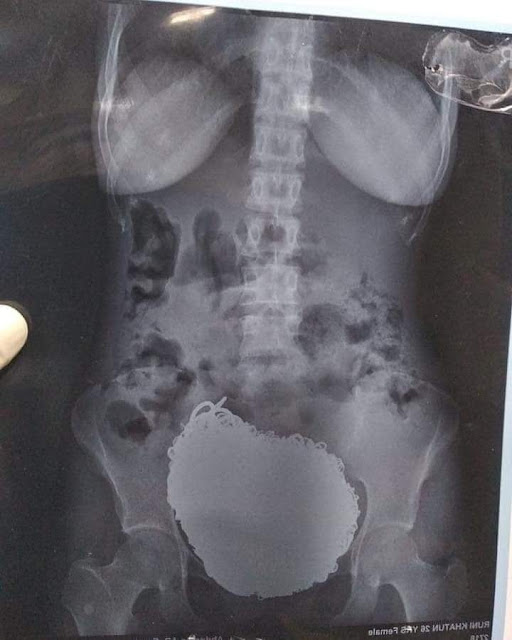

Pakar bedah di India terkejut selepas mereka mengeluarkan barang kemas dan syilling bernilai RM271,911.20 dari perut seorang pesakit wanita.

Ketika dibedah, doktor mengeluarkan 60 utas rantai, 80 bentuk anting-anting, 46 keping duit syilling, 8 loket, 11 anting-anting hidung, 4 kunci, 5 rantai kaki dan satu jam muka dari perut pesakit.

| X-Ray Barang Kemas dalam perut mangsa |

Doktor Siddharta Biswas berkata, "Pesakit terlalu lemah dan kurus ketika dibawa ke hospital. Keadaan dia sangat kritikal dan memerlukan sekurang-sekurangnya lima botol darah.

Dalam pembedahan yang berlangsung selama satu jam 15 minit, doktor berjaya mengeluarkan sebarang bendasing dari perut pesakit. Keadaan Runi kini stabil.